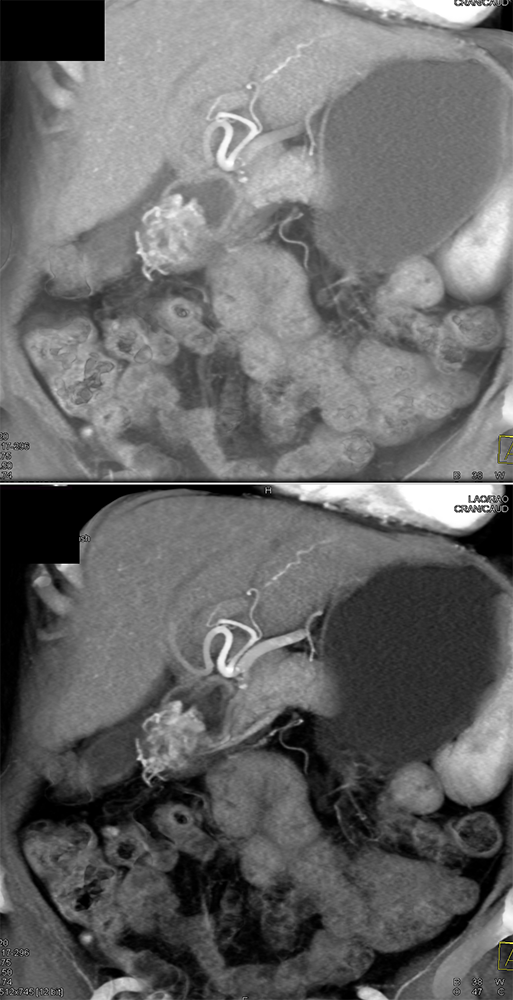

Suspected GI Bleed ![]() |